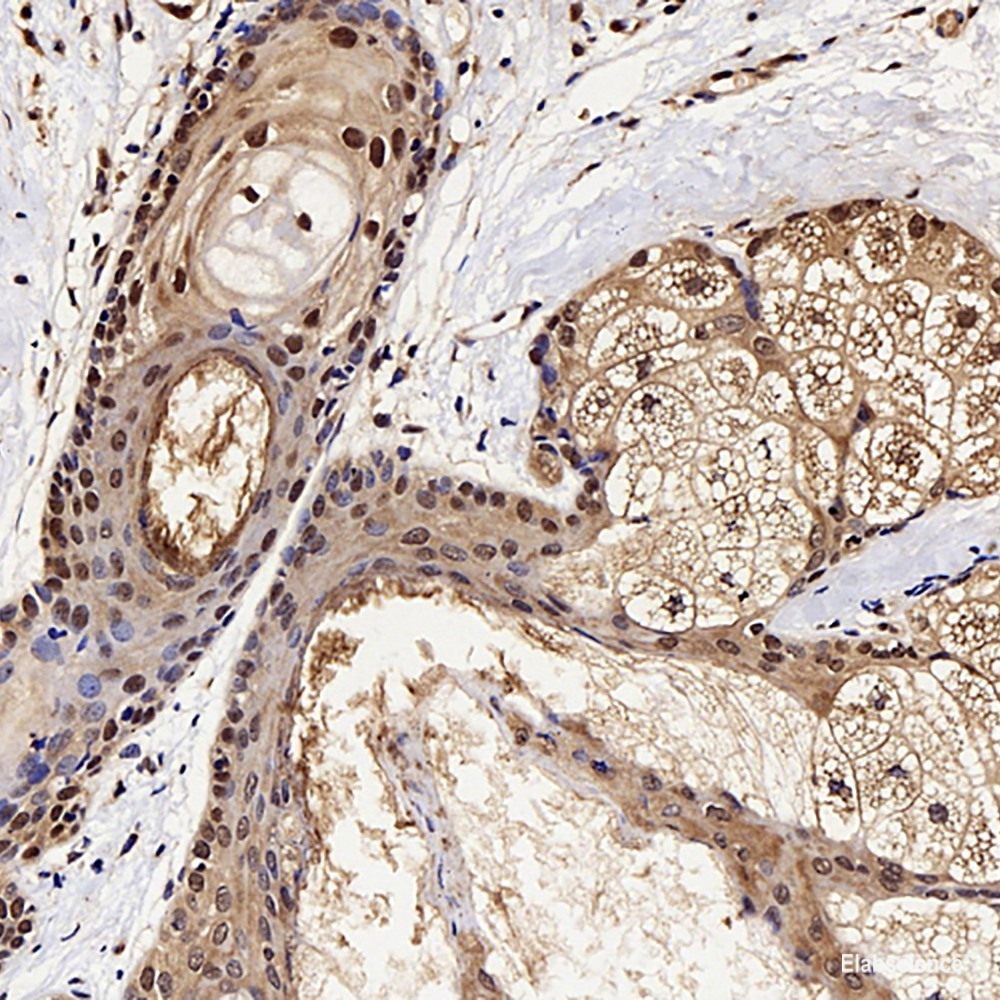

Product information "Anti-GSK3 beta"

| Application: | WB, IHC, IF |